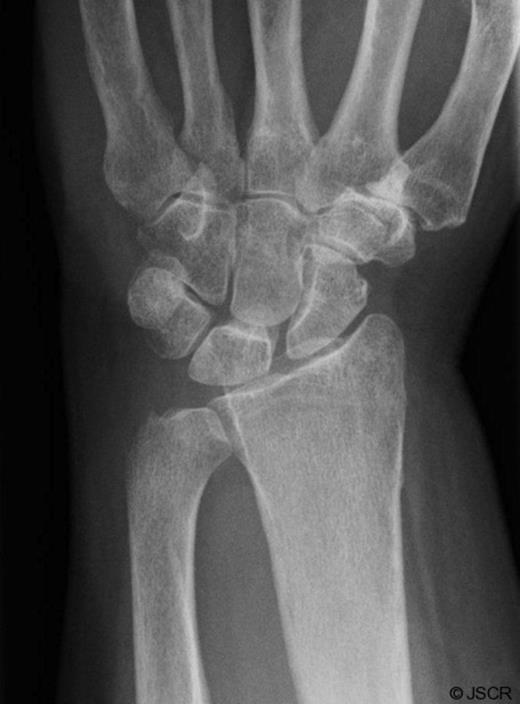

The patient agreed to a repeat biopsy and excision of the necrotic bone (Figure 4). Microscopy of the specimen again showed a florid granulomatous inflammatory process with areas of fibrinoid necrosis. Cultures isolated Mycobacterium tuberculosis.

Post-operative Xray of the wrist showing excision of the ulnar styloid